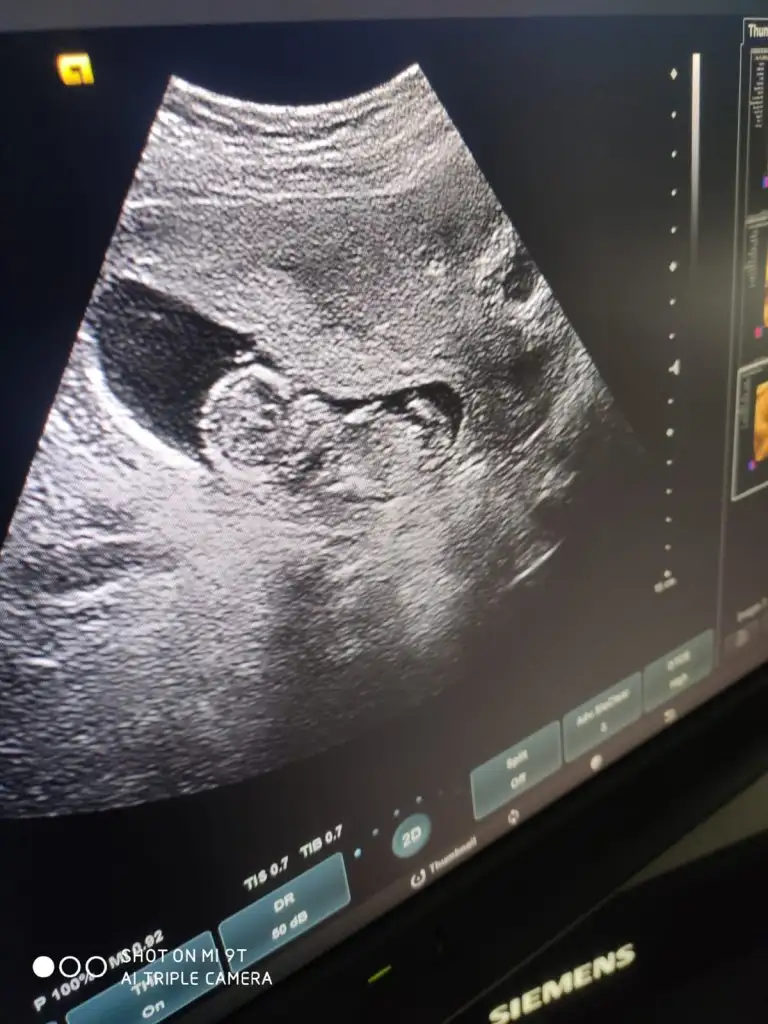

8 haftalık budaBaşka USG paylaşın![]()

Karından ise erkek vajinalsa kiz tabiki en iyi 11 12 13 haftalar8 haftalık buda

Karından bakıldı sonucu alınca yazarım size çok teşekkür ederimKarından ise erkek vajinalsa kiz tabiki en iyi 11 12 13 haftalar